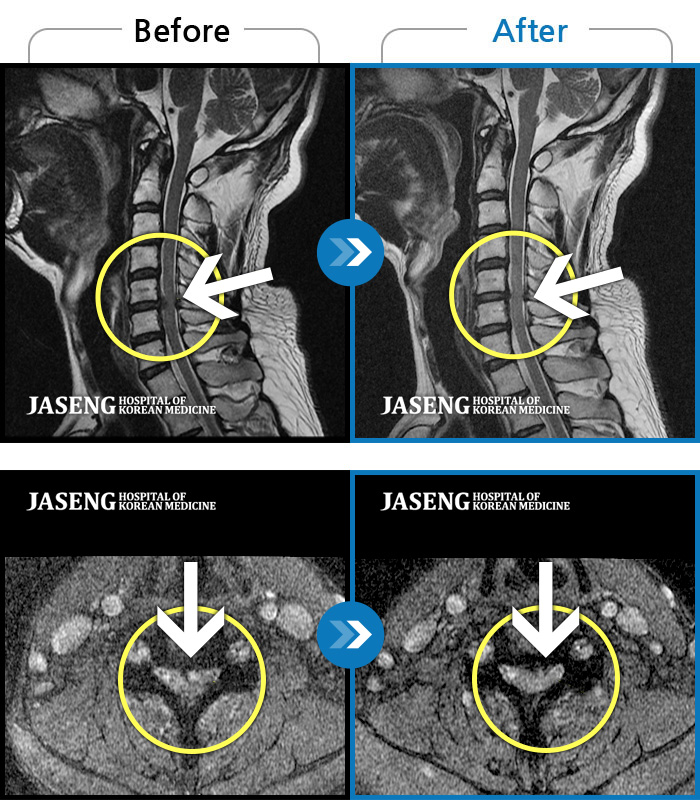

교통사고로 인해 기존의 퇴행성 디스크가 파열되어 극심한 경추의 통증과 손의 힘 빠짐, 손가락의 저림 증상을 호소하였음

2024.04.20 ~ 2024.11.02